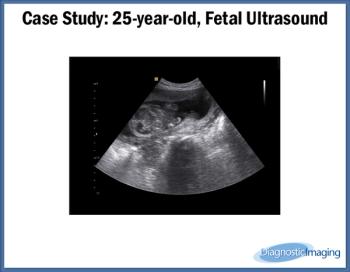

Case History: 25-year-old patient presents for fetal ultrasound.